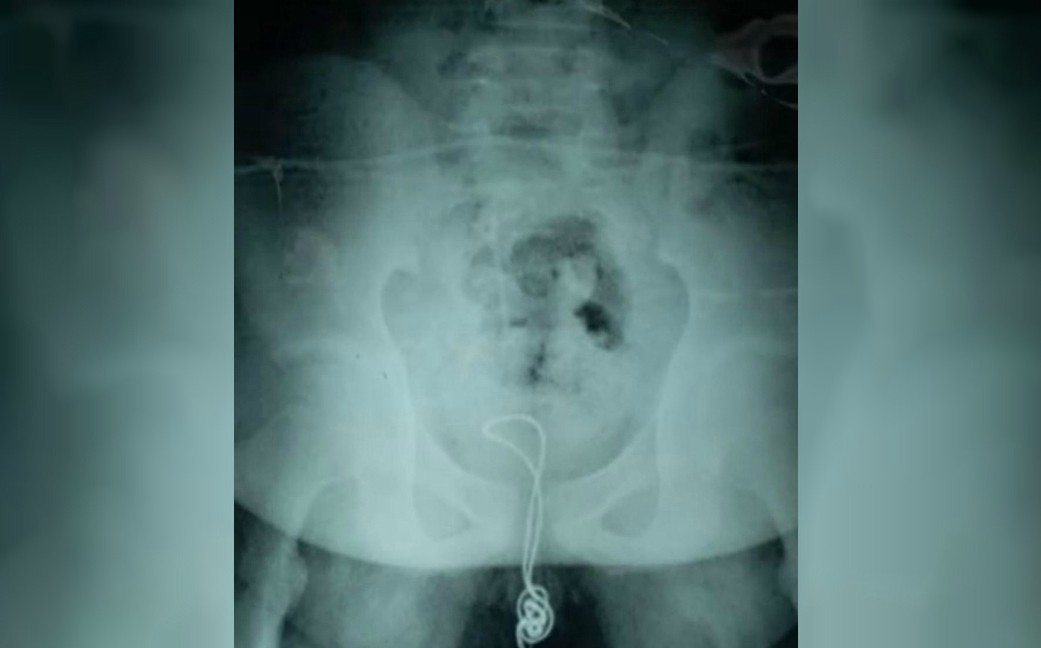

Movido por la curiosidad, un joven chino de 13 años se introdujo un cable USB por la uretra. Cuando intentó retirarlo, le fue imposible y comenzó a sentir dolor en su pene y vejiga.

Ante la emergencia, sus padres llevaron al adolescente a un hospital local en Linkou, al noreste de China, donde los doctores intentaron retirar el cable con la ayuda de lubricante, pero fue imposible, pues el objeto se había enredado en su interior.

Al día siguiente, el menor fue trasladado al Hospital Infantil Harbin, donde los médicos procedieron con una cirugía para extraer el cable. El joven fue dado de alta el pasado 3 de julio, a más de dos semanas de la operación.